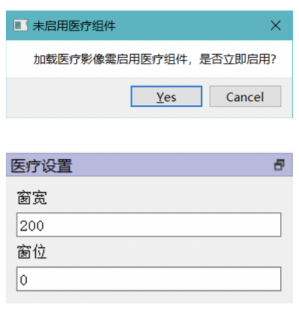

另外在医疗图像方向,EISeg支持打开CT和核磁共振产生的Dicom格式图像,如果打开图像的后缀为.dcm ,则会询问是否开启医疗组件,以支持用户自主设置窗宽和窗位。